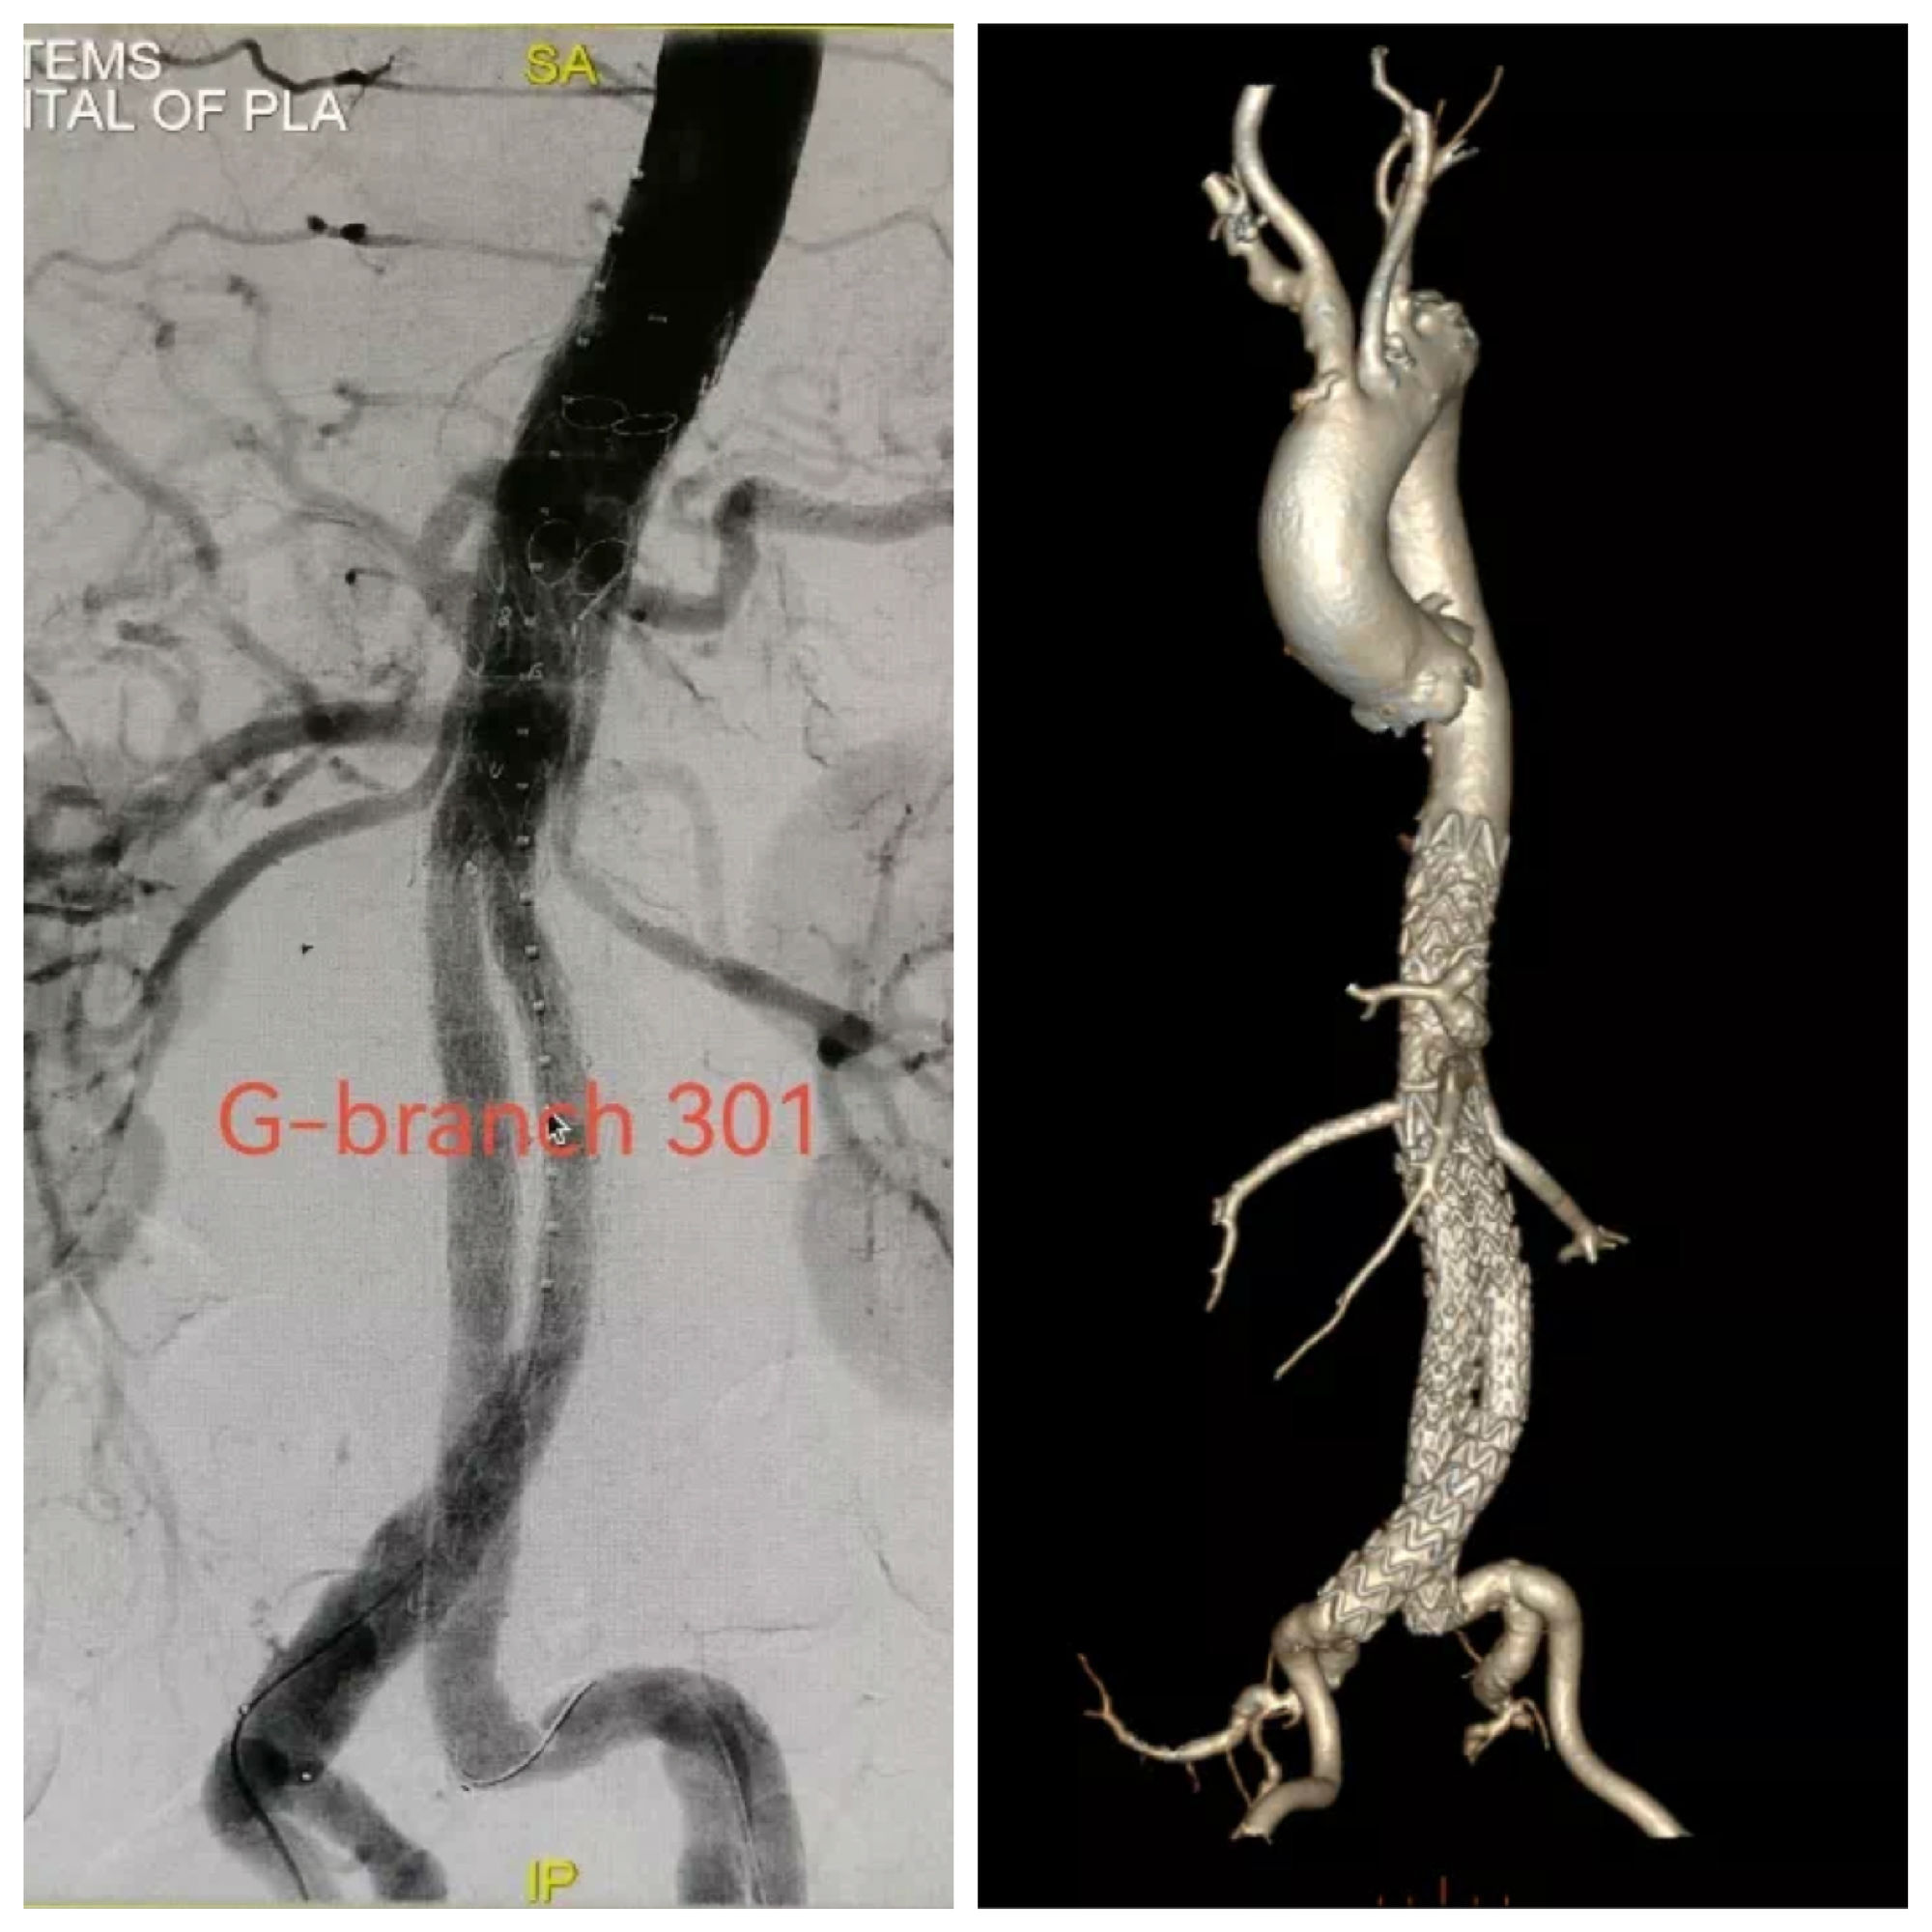

使用G-Branch™胸腹主动脉覆膜支架系统延长近端锚定区,腔内重建腹腔干、肠系膜上动脉及双肾动脉。

患者胸腹主动脉瘤隔绝完全,支架位置及形态良好,各分支动脉重建后血流通畅,无内漏发生。

术后,郭伟教授表示:“该患者为胸腹主动脉瘤先兆破裂急诊入院,既往EVAR术+肾动脉烟囱支架植入,肾动脉开口狭窄、病情危重,手术难度大。在急诊状况下应用G-Branch™及时重建了内脏动脉和肾动脉,让因I型内漏引起的濒临破裂的动脉瘤及时得到救治,这彰显了G-Branch非定制设计的优越性。混合内嵌分支设计理念的优越性在这例病变中得到了很好的呈现,在修复动脉瘤的同时最大化减少主动脉覆盖,从而有效降低截瘫并发症的发生风险。”